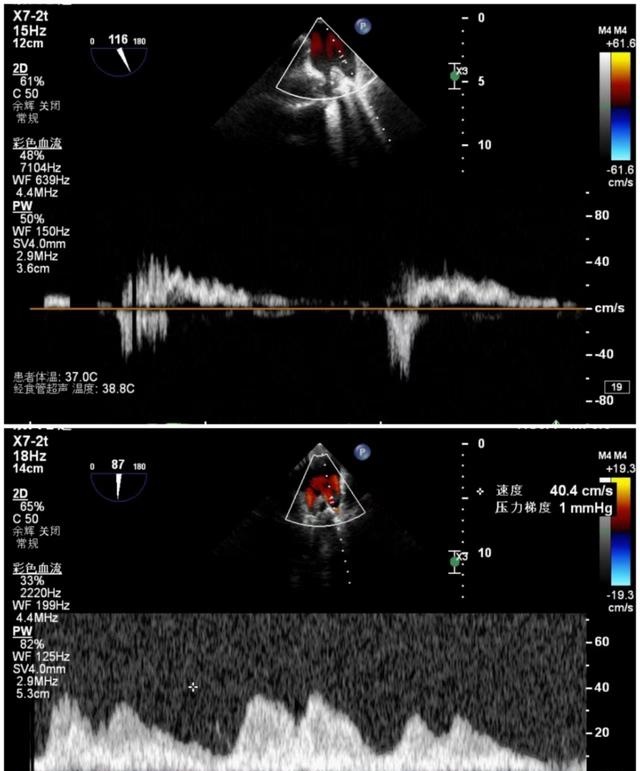

7月9日上午心内科联合麻醉科、胸外科等多学科,共同为陈奶奶开展手术,术前二尖瓣大量反流,反流程度5+,肺静脉反流明显,术后二尖瓣少量反流,反流程度1+,肺静脉反流消失,手术顺利结束。

手术前后肺静脉流速